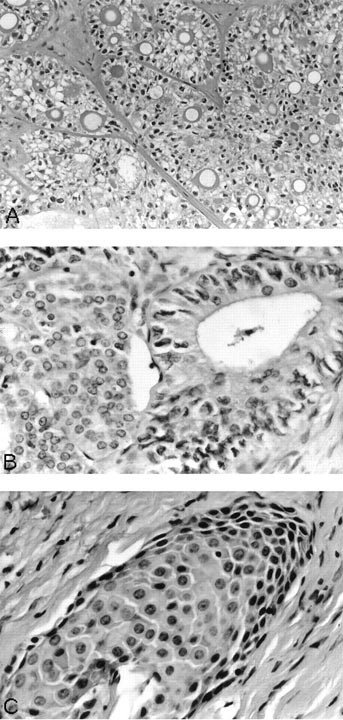

Mucoepidermoid carcinoma. A, nest of tumor cells with luminal mucin production. B, high-power view showing both ductal and epidermoid components. C, a nest of epidermoid component showing intercellular bridges and keratinized cells.